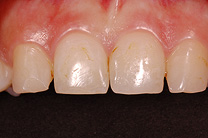

Fallbeispiel

Zum Vergrössern klicken